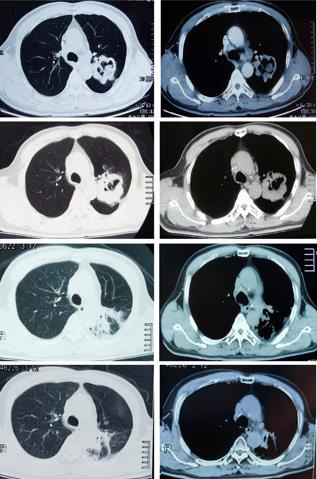

A 59-year-old man was admitted to our hospital after undergoing six courses of chemotherapy. The patient was diagnosed with lung adenocarcinoma of the left superior lobe with ipsilateral hilar and mediastinal lymph node metastasis (cT4N2M0, stage IIIB). An irregular, thick-walled hollow mass was observed on thoracic computed tomography (CT). He had smoked 1 pack per day for 40 years and had quit for approximately six months. He denied a history of underlying diseases and had no other relevant medical or family history. Due to the negative result of targetable driver gene mutations, such as epidermal growth factor receptor (i.e., EGFR), anaplastic lymphoma kinase (i.e., ALK), or BRAF, the patient had been treated with six courses of adequate chemotherapy with a combination regimen of pemetrexed plus carboplatin, although reexamination using chest CT revealed increased tumor volume, with efficacy evaluated as progressive disease (Figure 1A-1D). Because chemotherapy did not yield satisfactory control of the lesion, tissue samples were submitted for immunohistochemistry. Results revealed that the proportion of PD-L1 positive tumor cells accounted for > 50% of cells, which indicated that this patient was likely to benefit from immunotherapy. After cardiopulmonary function and thyroid function tests were performed to confirm that treatment could be tolerated, he was treated with the ICI, camrelizumab (200 mg once every two weeks), combined with thoracic radiotherapy (intensity-modulated radiation therapy [IMRT], DT: 6600cGy/33F) (Figure 2). Soon after, the patient experienced significant improvement in symptoms of cough and shortness of breath. Chest CT confirmed reduction in tumor size (Figure 1C). The patient was treated with camrelizumab for consolidation treatment (200mg once every three weeks) and underwent 12 cycles. After three months, the tumor had disappeared (Figure 1D) and no severe immune-related adverse events (irAEs) have been observed to date, two years after the end of radiotherapy (Figure 3). Therapeutic efficacy was evaluated as PR. It is worth noting that the patient developed transient reactive cutaneous capillary endothelial proliferation (RCCEP) after two cycles of camrelizumab, which may indicate that he was particularly sensitive to this ICI. The objective curative effect and survival benefit of immunotherapy may be encouraging.

Figure 1: Computed tomography (CT) images before and after

treatment.

a) Chest CT images at initial admission.

b) Chest CT images after six courses of chemotherapy.

c) Chest CT images four months after immunoradiotherapy.

d) Chest CT images after 24 months of immunoradioatherapy.